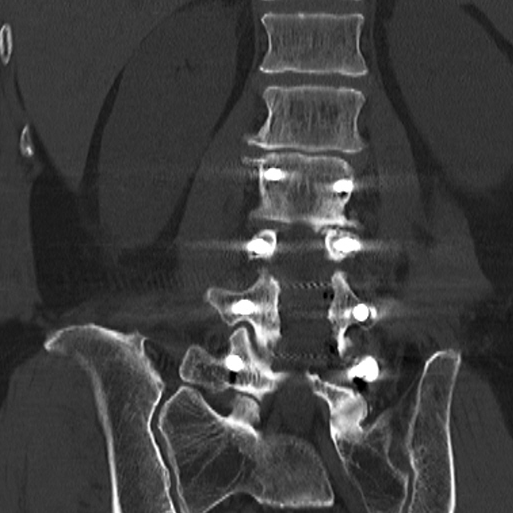

陈勇主任团队顺利为患者置入椎弓根螺钉。术后患者腰腿痛症状较术前明显缓解,肢体活动无障碍,术后3天即在脊柱支具外固定的辅助下下地行走,术后第7天患者恢复情况良好,顺利出院。

▲术中椎弓根螺钉精准置入

▲术后复查X线、CT